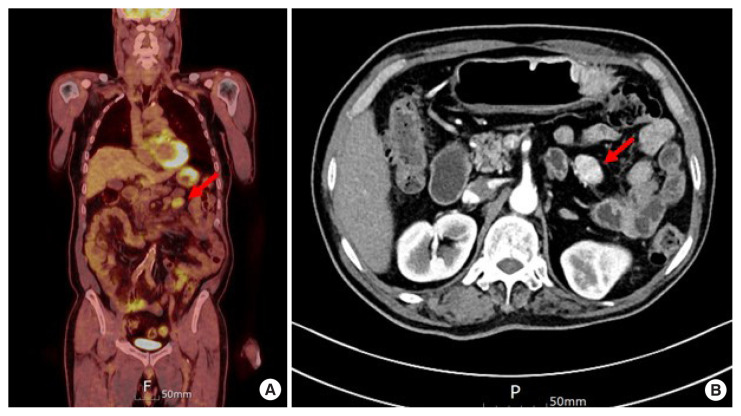

众所周知,分化良好的甲状腺癌(WDTC)会向骨和肺进行远处转移,而腹腔内和肠系膜转移则非常罕见。在此,我们报告了一例WDTC腹腔内肠系膜转移病例。一名 62 岁的男性因患滤泡性甲状腺癌接受了甲状腺叶切除术。一年后发现肺转移。患者同时接受了肺楔形切除术和甲状腺全切除术。11年后,患者血清甲状腺球蛋白水平升高。在检查中发现了肺部转移灶和肠系膜肿块。手术切除了肺部和肠系膜的两个病灶。肠系膜肿块经病理诊断为转移性 WDTC。

Distant metastases of well-differentiated thyroid cancers (WDTCs) to bone and lungs are well known, while intra-abdominal, mesenteric metastases are very rare. Herein, we report a case of intra-abdominal, mesenteric metastasis of WDTC. A 62-year-old man underwent thyroid lobectomy for follicular thyroid cancer. One year later, lung metastasis was observed. The patient simultaneously underwent lung wedge resection and complete thyroidectomy. Eleven years later, serum thyroglobulin level was elevated. On the work-up study, a metastatic lesion in the lungs and a mass in the mesentery were identified. Two lesions of the lung and mesentery were surgically resected. The mass in the mesentery was pathologically diagnosed as metastatic WDTC.